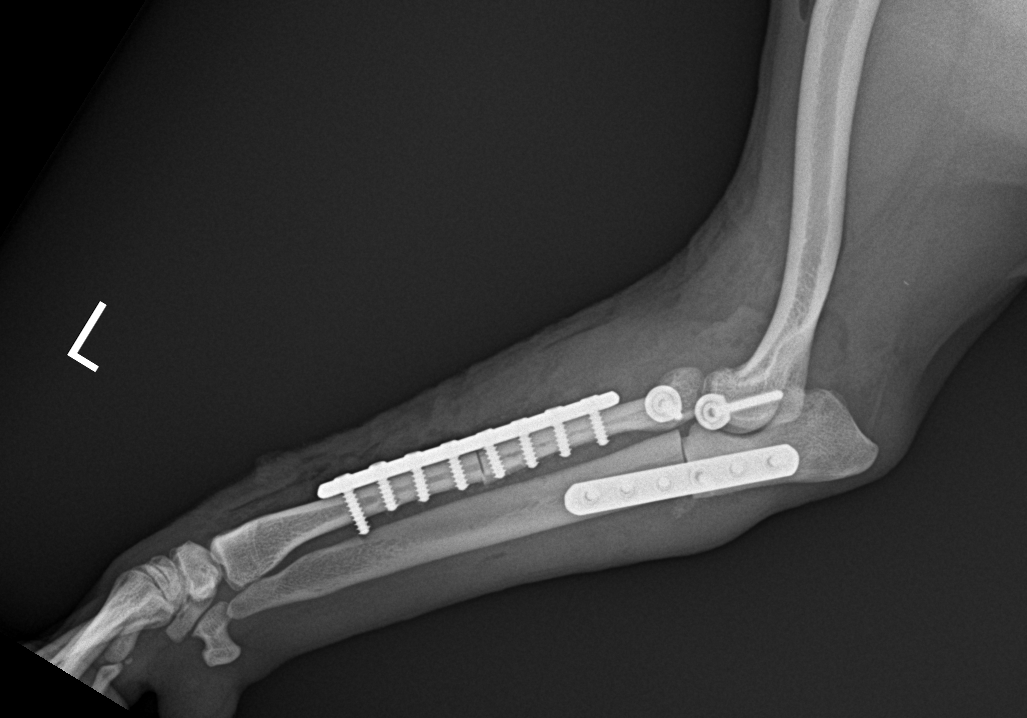

2歳の柴犬ちゃんが、生まれてすぐに痛めた肘に徐々に痛みが出てきたとのことで、主治医から診察と必要があれば手術をして欲しいと連絡がありました。CTでは橈骨頭が外側に脱臼して変位していました。また回転性の変形を伴っています。同時に尺骨にも湾曲が認められています。このような変形矯正には3Dプリンターで模擬手術を行いあらかじめシミュレーション手術をしておくと時間の短縮と正確な変形矯正が可能となります。このようなテクノロジーを動物医療にもどんどん取り入れていきたいと思います。また、骨きり部位にはPRFと自家海綿骨移植を行い治癒促進を期待します。